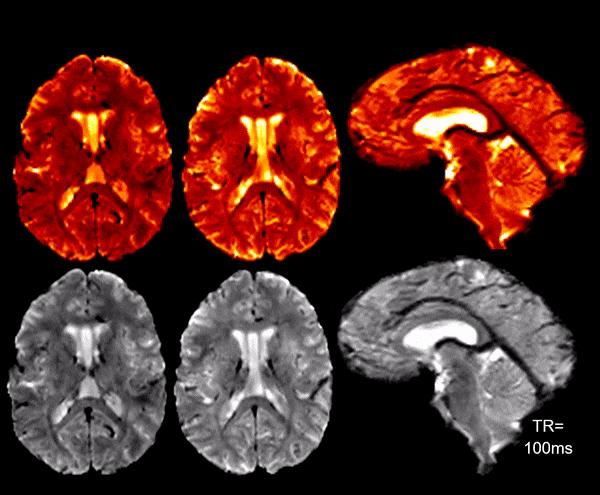

High SNR/CNR allows for real-time 7T MRI for brain pulsatility and CSF flow measurements.

Radiofrequency (RF) Research Facility/University of Pittsburgh